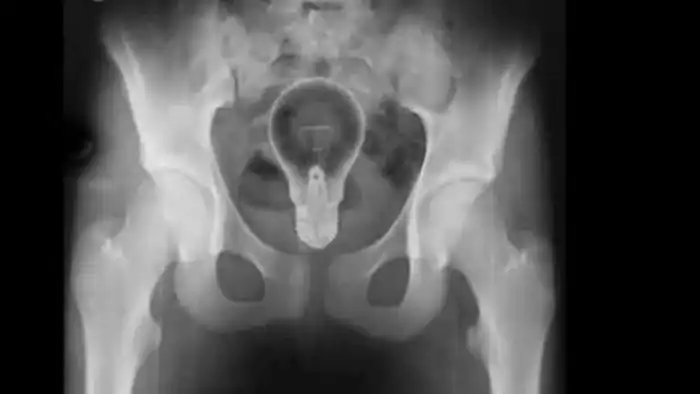

Обычно лампочки, ради интереса, засовывают в рот. Здесь же интерес, видимо, выдался другим.